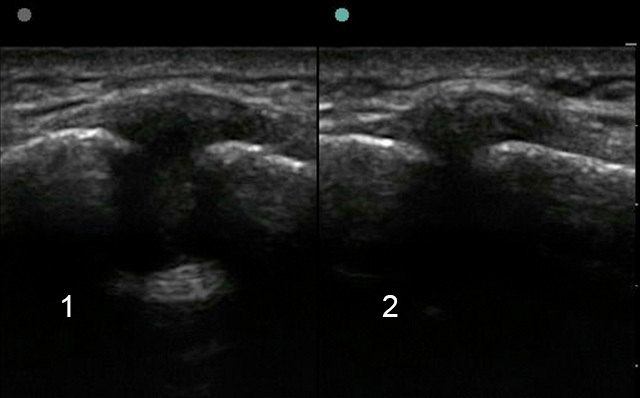

Image - Épaule : Liquide dans l'articulation acromio-claviculaire

1. Articulation acromio-claviculaire (AC)

2. Toucher de l'autre épaule